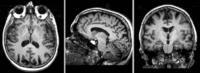

Registration Results

Exam 1 co-registered

Exam 1 co-registered: FLAIR and T2 aligned with T1

Exam 2 co-registered

Exam 2 aligned to Exam 1

Exam 2 aligned to Exam 1 (showing FLAIR and T2 of exam 2 also)